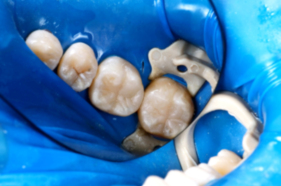

Moderní kompozitní materiály dovolují jejich použití kdekoli v ústech, tedy nejen na předních zubech. Při dodržování nejpřísnějších kritérií při jejich zhotovování, z nichž nejdůležitější je zamezení přístupu vlhkosti, jsou zhotovené bílé výplně více než rovnocennou náhradou amalgámu. Ve srovnání s amalgámem trvá jejich zhotovení o něco déle, protože je důležité je vrstvit po malých částech a každou část vytvrdit „modrým“ světlem, ale konečný výsledek je kvalitnější.

Kofferdam je napínatelná blána, kterou používáme k izolaci zubů, na nichž pracujeme, abychom je mohli udržet v suchu. Normálně jsou zuby omývány slinami, což jim prospívá, ale často to znemožňuje správné ošetření zubu právě pomocí bílé výplně nebo ošetření kořenových kanálků. V bláně se vytvoří otvory, kterými se blána navlékne na zuby až ke krčkům a uchytí speciálními sponami. Následně je blána vypnuta na rámeček. Nasazení je rychlé a snadné, pacient je v naprostém pohodlí a díky tomuto úkonu se zamezí jakémukoli průniku tekutin jak z úst, tak do úst. Pod blánou je možné polykat dle potřeby a po dobu ošetření dýchat nosem.